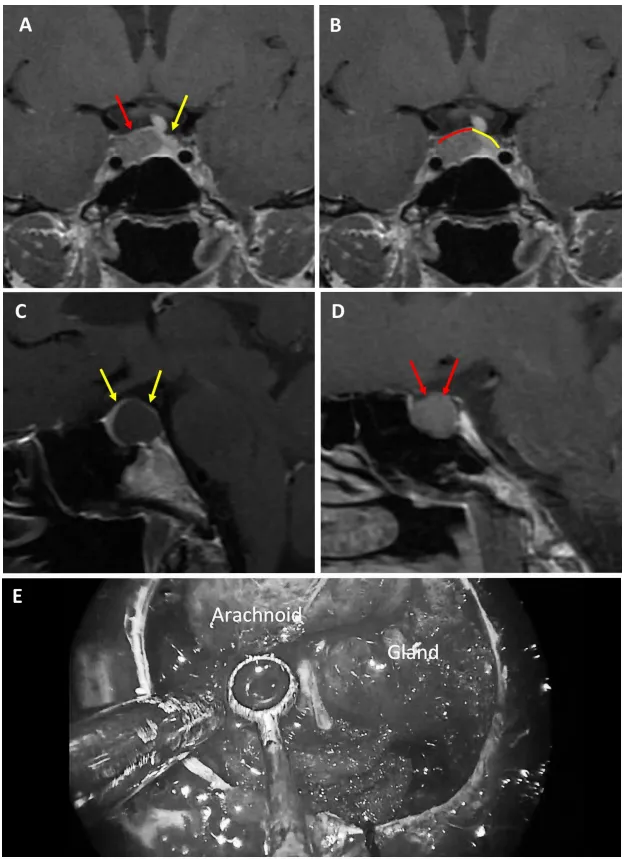

3薄弱型鞍隔屏障案例

图6:59岁女性泌乳素腺瘤患者。a、b术前MRI:红色箭头指示厚度小于1毫米的强化屏障区。c、d术前MRI:红色标记线标示薄弱屏障位置。e、f术中图像:可见由蛛网膜构成的屏障结构。

图7:69岁女性生长激素腺瘤患者。a、b术前MRI:黄色箭头指示厚度小于1毫米的强化屏障区。c、d术前MRI:红色标记线标示薄弱屏障位置。e、f术中图像:可见由蛛网膜构成的屏障结构。